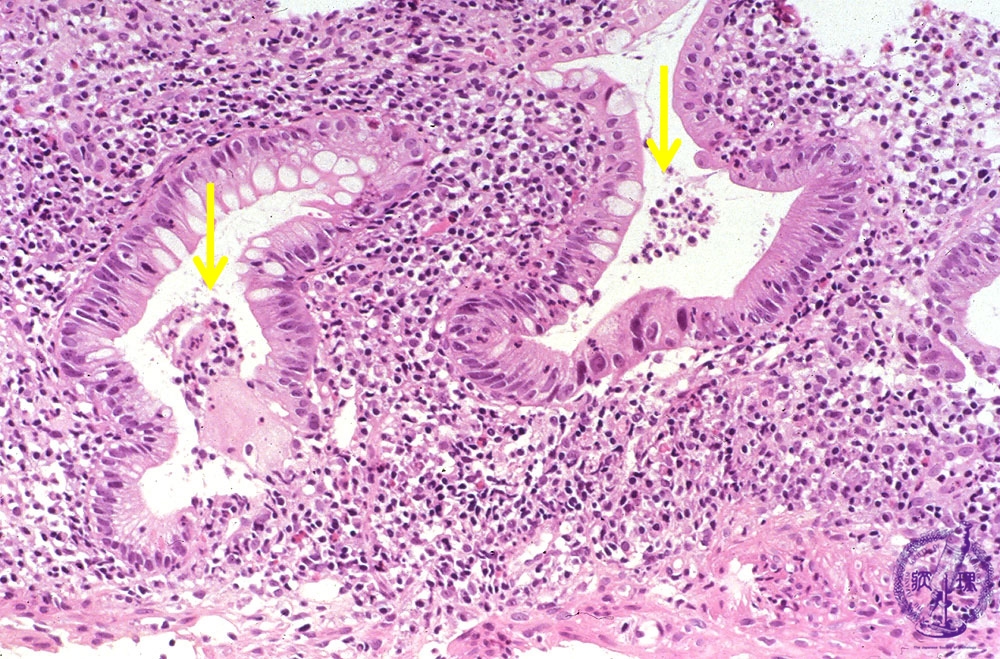

Microscopic view (H&E stain, high power): Acute ulcerative colitis with severe inflammation including crypt abscess formation.